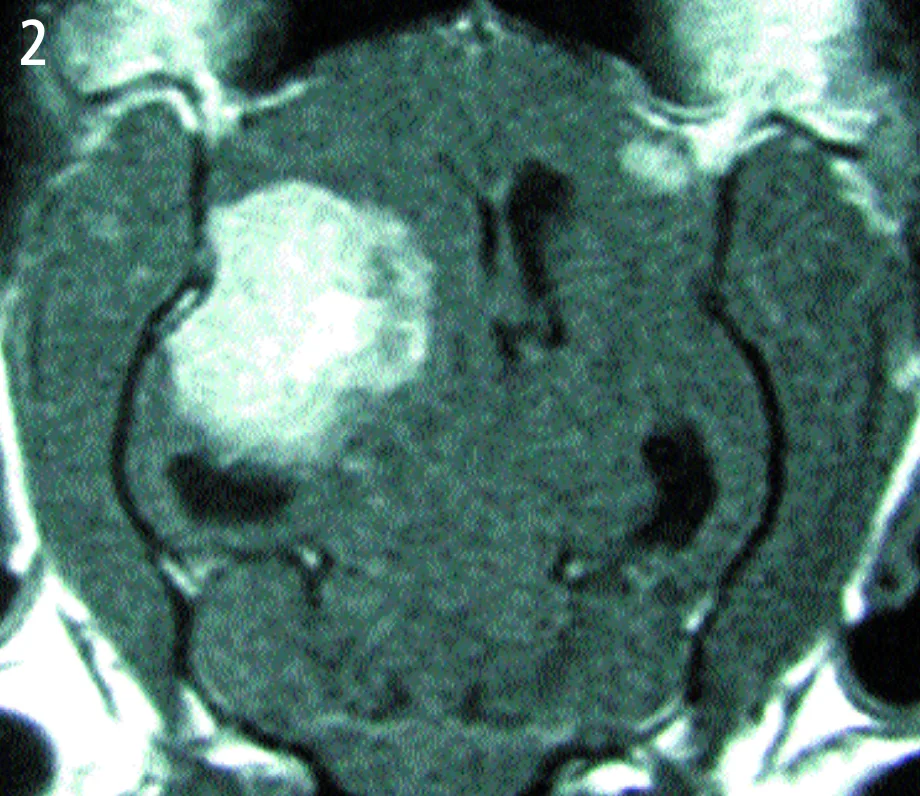

Dorsal view—T1-weighted, contrast-enhanced magnetic resonance image

A large, left-sided cerebral mass, evident on both images.

The mass is uniformly contrast-enhancing on the MRI, appears to have a broad-based attachment to the skull, and has distinct margins-all of which are characteristic of intracranial meningiomas. The most likely diagnosis is meningioma. A smaller, right-sided mass can be seen on the dorsal image. This mass also has characteristic features of meningioma. Both masses were removed and confirmed histologically as meningiomas. The cat made a full recovery.

Dorsal view—T1-weighted, contrast-enhanced magnetic resonance image